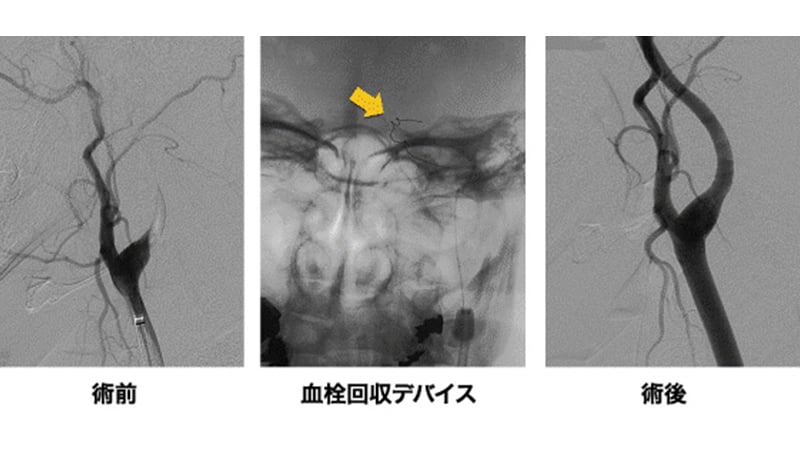

tPA静注が適応ではない症例、発症より3時間以上が経過している症例、tPAを投与しても改善が思わしくない症例では、緊急で血管内手術を行います。閉塞血管にカテーテルを誘導して血栓溶解薬を局所的に投与したり、風船で狭い血管を膨らませたりして血行再建術を行います。

MERCIやPenumbraという新しい血栓回収デバイスを使った血行再建術にも対応しており、これまでは再開通できなかったような病変も救えるようになりました(図7)。このデバイスが使用できない近隣の診療所や病院からも、いつでも緊急症例を受け入れられるような体制を整えております。